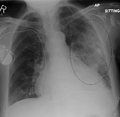

AP CXR showing left lower lobe pneumonia associated with a small left sided pleural effusion

AP CXR showing right lower lobe pneumonia

AP CXR showing pneumonia of the lingula of the left lung

Right upper lobe pneumonia as marked by the circle.- Left upper lobe pneumonia with a small pleural effusion.